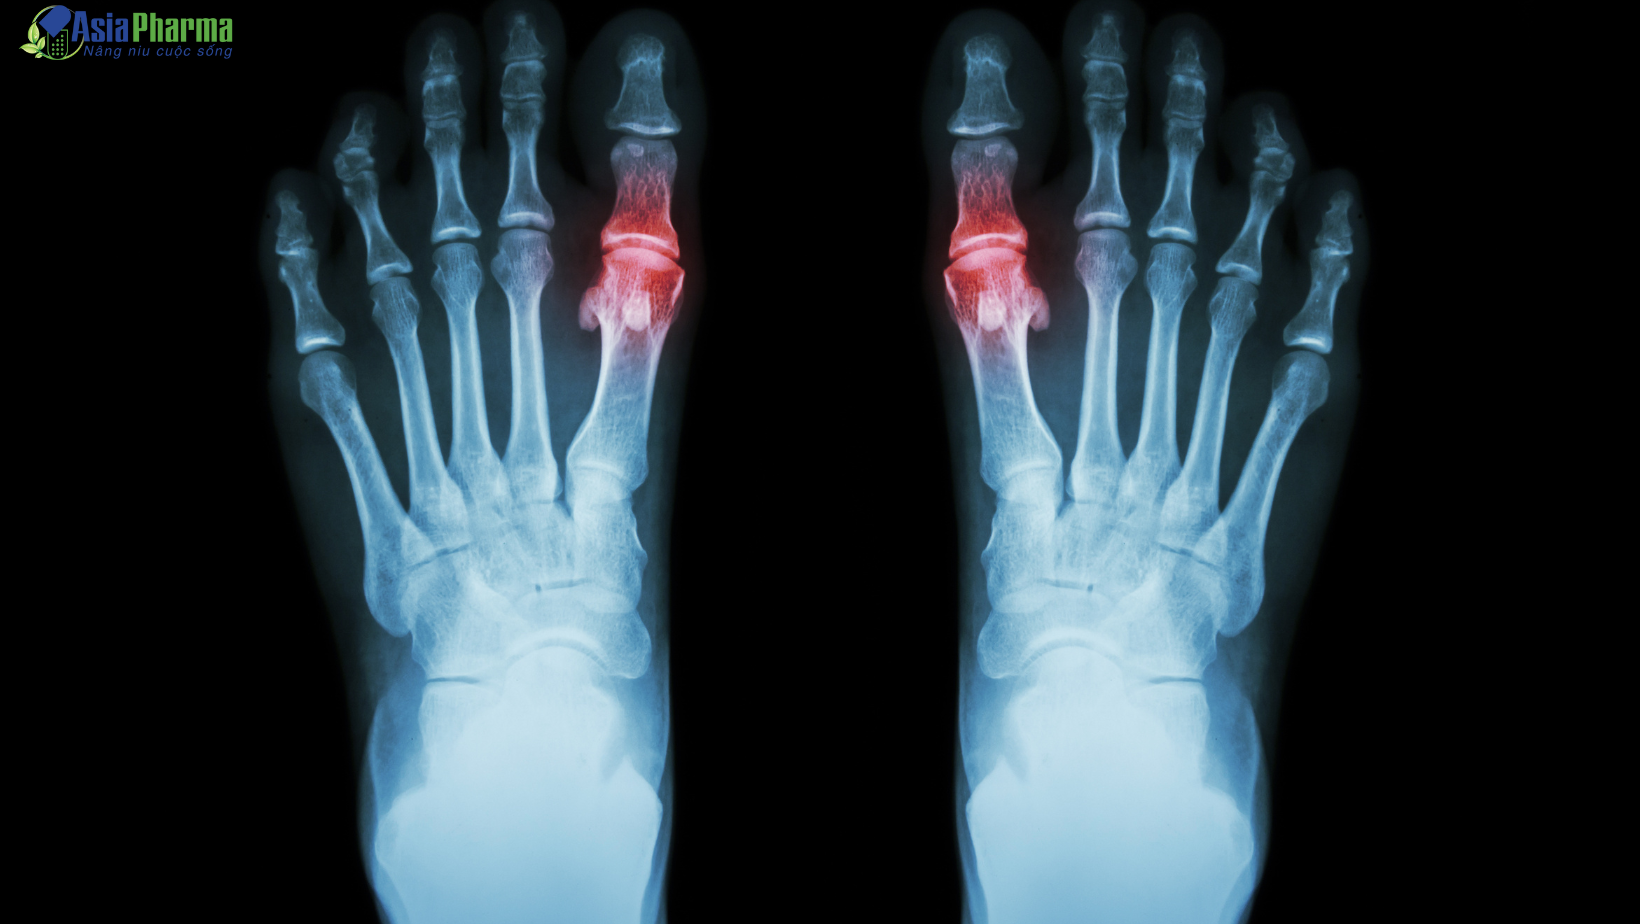

• Các nguyên nhân ngoài khớp: thường gặp do các rối loạn chuyển hóa (tăng acid uric trong bệnh gút), bất thường trong hệ thống miễn dịch gây tổn thương các thành phần trong khớp (bệnh viêm khớp dạng thấp) các tình trạng này làm ảnh hưởng tới hoạt động và cấu trúc của khớp, từ đó gây viêm khớp.